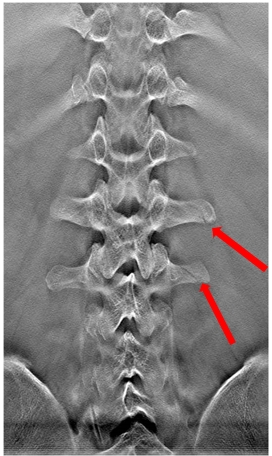

病例四:男,35歲。摔傷入院。

斷層融合能夠清晰顯示腰椎橫突骨折。